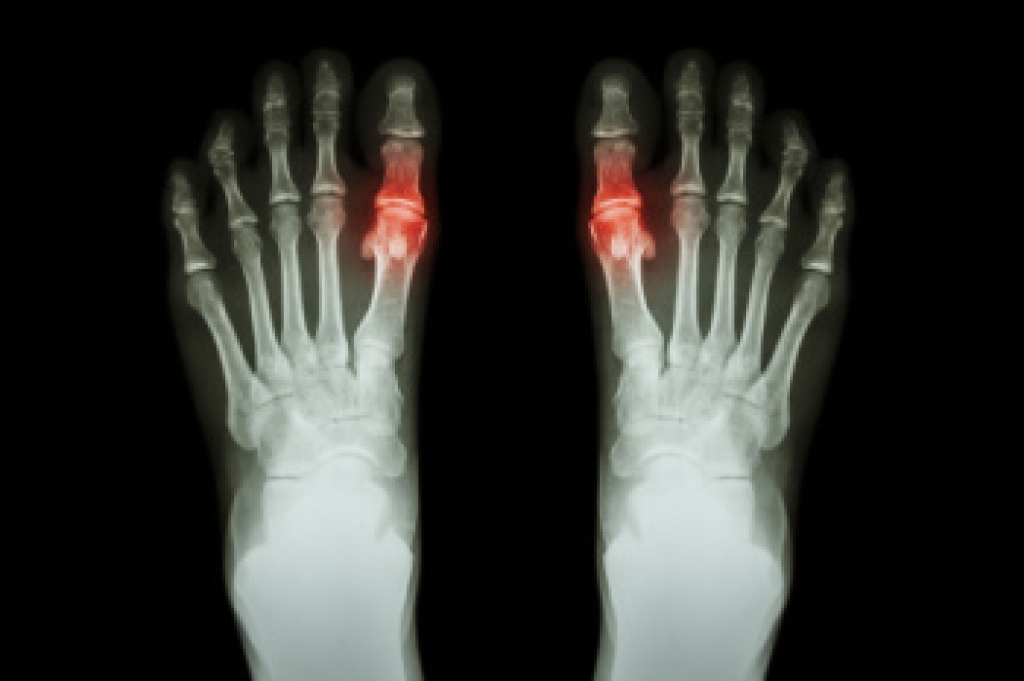

As people age, changes in strength, balance, vision, and joint health can lead to gait disorders that increase the risk of falls and limit independence. A gait disorder may involve shortened steps, shuffling, unsteadiness, or asymmetrical walking patterns. These issues can stem from arthritis, neurological conditions, foot deformities, or muscle weakness. Pain in the feet or ankles often contributes to altered walking habits that place strain on other parts of the body. Early identification is important, as many gait disorders can be improved with targeted exercises, proper footwear, assistive devices, or custom orthotics. A podiatrist can evaluate foot mechanics and recommend ways to improve stability and comfort. Regular foot exams are especially important for older adults to detect changes before they lead to serious complications. If walking has become more difficult or unsteady, it is suggested that you schedule an appointment with a podiatrist for a full assessment and treatment options.

When people age, some common issues that may occur are bone density loss, dry skin, poor circulation, and rough brittle nails. These issues may also affect your foot health if the necessary steps are not taken to alleviate the problems.

It is important to take care of your feet because feet that are injured or diseased can affect your overall health. Having painful feet hinders your ability to do daily activities or may decrease your willingness to do the things that you need to do.